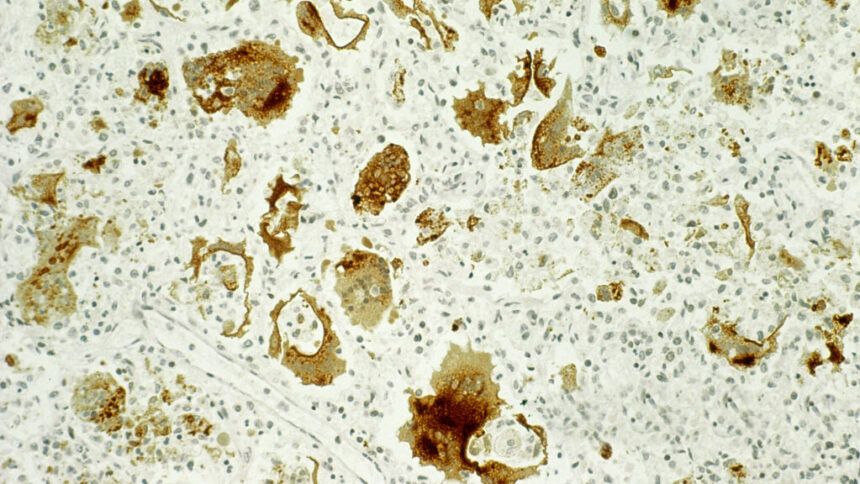

Phyllis Greenberger recounted her experience with measles before the vaccine was available, which led to her developing encephalitis and being hospitalized for weeks. Although she faced occasional aphasia symptoms in the years that followed, they eventually subsided.